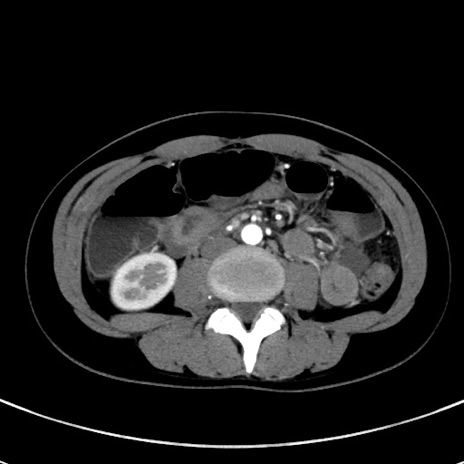

症例17(横断像)

【症例】20歳代女性

【主訴】嘔吐、下腹部痛

【現病歴】昨日夕食後に嘔吐し下腹部痛が出現。本日になっても嘔吐持続し改善しないため来院。

【身体所見】意識清明、BT 37.2℃、BP 108/67mmHg、腹部:平坦、やや硬、下腹部正中から右にかけて圧痛あり、反跳痛軽度あり、tapping pain(+)。

【データ】WBC 13600、CRP 14.94